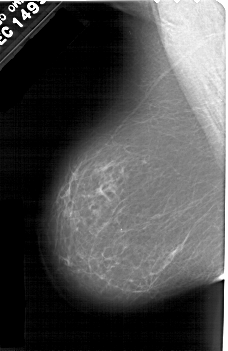

A_1601_1.RIGHT_CC

RIGHT_CC LINES 5491 PIXELS_PER_LINE 3436 BITS_PER_PIXEL 12 RESOLUTION 43.5 OVERLAY

FILE: A_1601_1.RIGHT_CC.OVERLAY

TOTAL_ABNORMALITIES 1

ABNORMALITY 1

LESION_TYPE CALCIFICATION TYPE PLEOMORPHIC DISTRIBUTION LINEAR

ASSESSMENT 4

SUBTLETY 2

PATHOLOGY BENIGN

TOTAL_OUTLINES 1

BOUNDARY